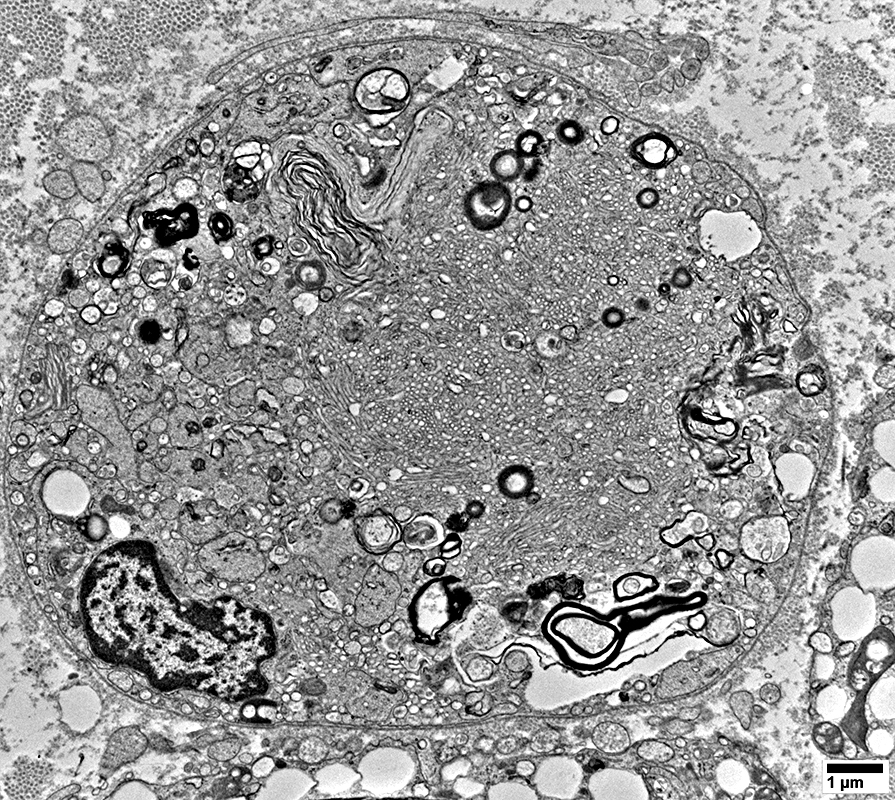

Myelin Damage: Lipid Droplets & Ovoids in Schwann cells

From: R Schmidt

Myelin Damage: Lipid Droplets & Myelin debris in Schwann cells

Myelin Damage: Lipid Droplets & some Myelin debris in Schwann cells